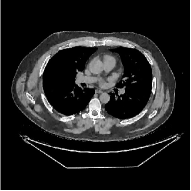

This paper was inspired by a simple observation related to our recent study [34]: for the penalized weighted-least squares (PWLS) reconstruction method using prior with a learned ST (PWLS-ST-) [34], the sparsification error histograms match a Laplace distribution over the iterations; see Fig. 1. The question then arises, “Does the learned prior experience model mismatch in testing stage?” To answer this question, we aim to investigate learned STs for regularization. This paper

The term denotes a -based sparsification error [3, 4, 5]. We expect to be more robust to sparsity model mismatch than the -based sparsification error used in [34, 36]. Fig. 1 shows histograms of sparsification error at different outer iterations of the PWLS-ST- method. Over the iterations, the sparsification error histograms appear more like a Laplace distribution than a Gaussian distribution. This observation suggests that the proposed prior model is more suitable than the prior model for PWLS-ST-based reconstruction. Section III-B1 shows that the proposed -based sparsification error term, , improves the accuracy of reconstruction compared to the prior model in [34, 36].